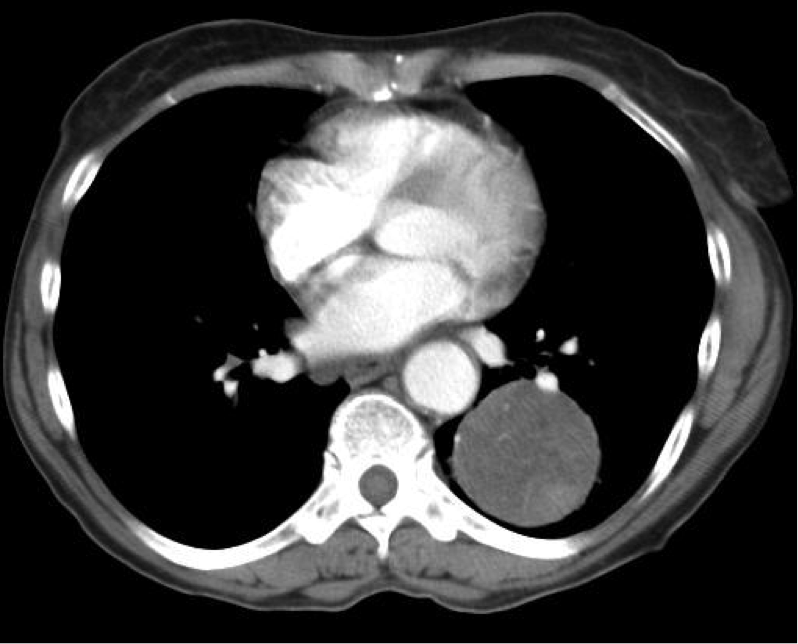

Laboratory tests. Chest radiography revealed a well-circumscribed mass in the left lower lobe (Figure 1). Contrast enhanced CT of the chest revealed a well-defined mass, 5.4 cm in diameter in the left lower lobe, containing areas of attenuation suggestive of fat deposition—a characteristic of pulmonary hamartoma (Figure 2).

Figure 2. Contrast enhanced CT image of pulmonary hamartoma.